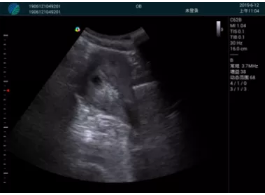

病例一:

清晰顯示孕囊,通過軟件包計算孕齡7w+6d

M20實時引導(dǎo),術(shù)中清晰顯示孕囊被破壞和抽吸針的過程,清晰顯示吸引針

抽吸結(jié)束后縱切子宮,孕囊已被完全抽吸,未見明顯殘留

橫切子宮,發(fā)現(xiàn)右側(cè)宮腔靠近宮角處有少許脫模樣殘留

M20引導(dǎo)下,抽吸針找到右側(cè)宮角處再次清掃

二次抽吸后再次進(jìn)行超聲檢查,宮腔未見殘留,宮腔線清晰顯示

超聲引導(dǎo)下可視化人流是技術(shù)安全性的保障,一般對人流術(shù)設(shè)備預(yù)算不高,M20具備婦產(chǎn)科軟件包,且穿透力圖像質(zhì)量好,既滿足人流引導(dǎo)需要,也可用于床旁超聲的需求。